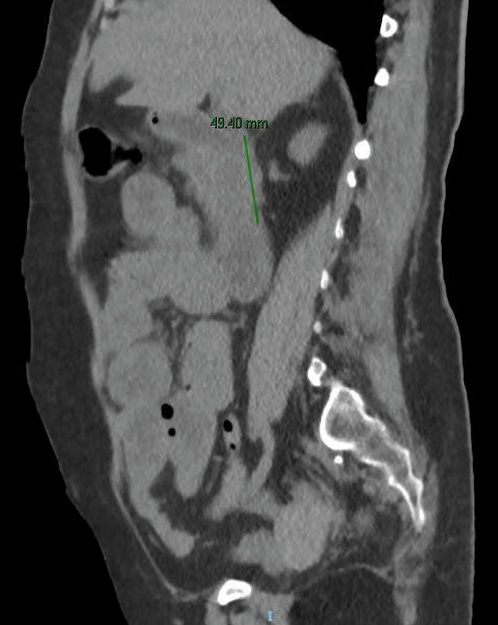

An abdominal computed tomography was performed (without intravenous contrast because the patient was allergic). It showed dilation of the second and third duodenal portions, with wall thickening and rarefaction of the adjacent fat, in relation to inflammatory changes that seemed to affect a segment of about 5 cm (Fig. 2). Symptoms persisted, so a magnetic enteroresonance was done and mild dilation and slight inflammatory changes were found which affected a segment of about 3 cm of the second duodenal portion. The involvement seemed to have improved since the previous computed tomography. The histological study of gastric and duodenal biopsies showed colonization of acini by S. stercolaris in both the antrum and the duodenum (Fig. 3). A stool test confirmed infection with this parasite. Treatment of S. stercolaris hyperinfestation with ivermectin and albendazole was initiated, with progressive tolerance and clinical improvement. She completed 18 days of treatment with antihelminthic drugs until repeated stool tests showed no presence of the parasite. Five months later the patient had a new exacerbation of acquired thrombotic thrombocytopenic purpura, which was treated again with glucocorticoids, plasma exchange, and rituximab, but did not show any gastrointestinal symptoms and stool tests remained negative with prophylaxis with ivermectin.

Fig. 2: Abdominal computed tomography image without intravenous contrast showing dilation of the second and third duodenal portions, with wall thickening and rarefaction of the adjacent fat, in relation to the inflammatory changes that seem to affect a segment of about 5 cm.